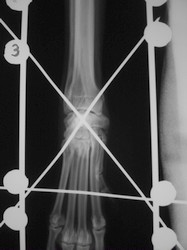

PRÁCTICAS CURSO DE FIJACIÓN EXTERNA PERFECCIONAMIENTO.

Artrodesis carpo.